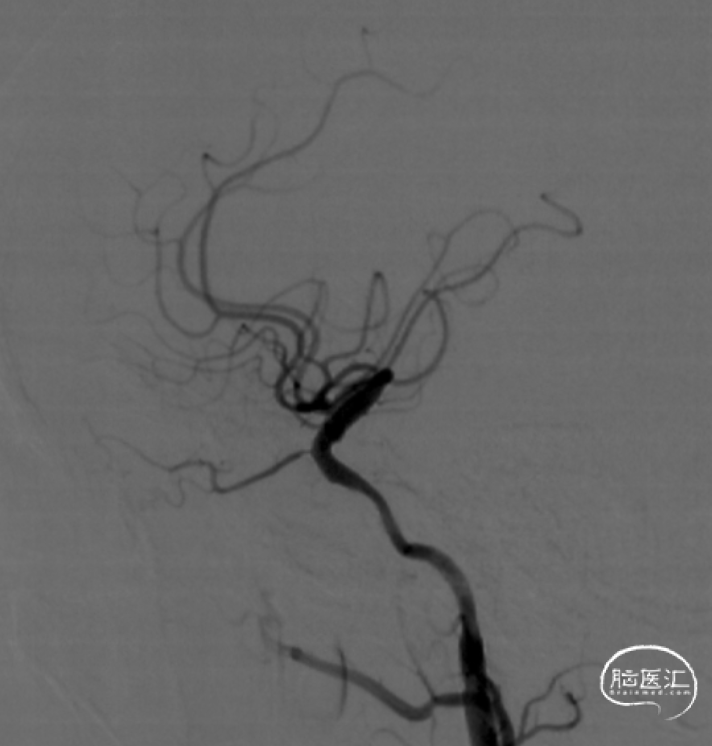

造影见右侧颈内动脉闭塞、颈内动脉开口可见残端,眼动脉向C6段代偿 Hasan分型为B型。

术后CT未见异常,患者无新发神经功能障碍。